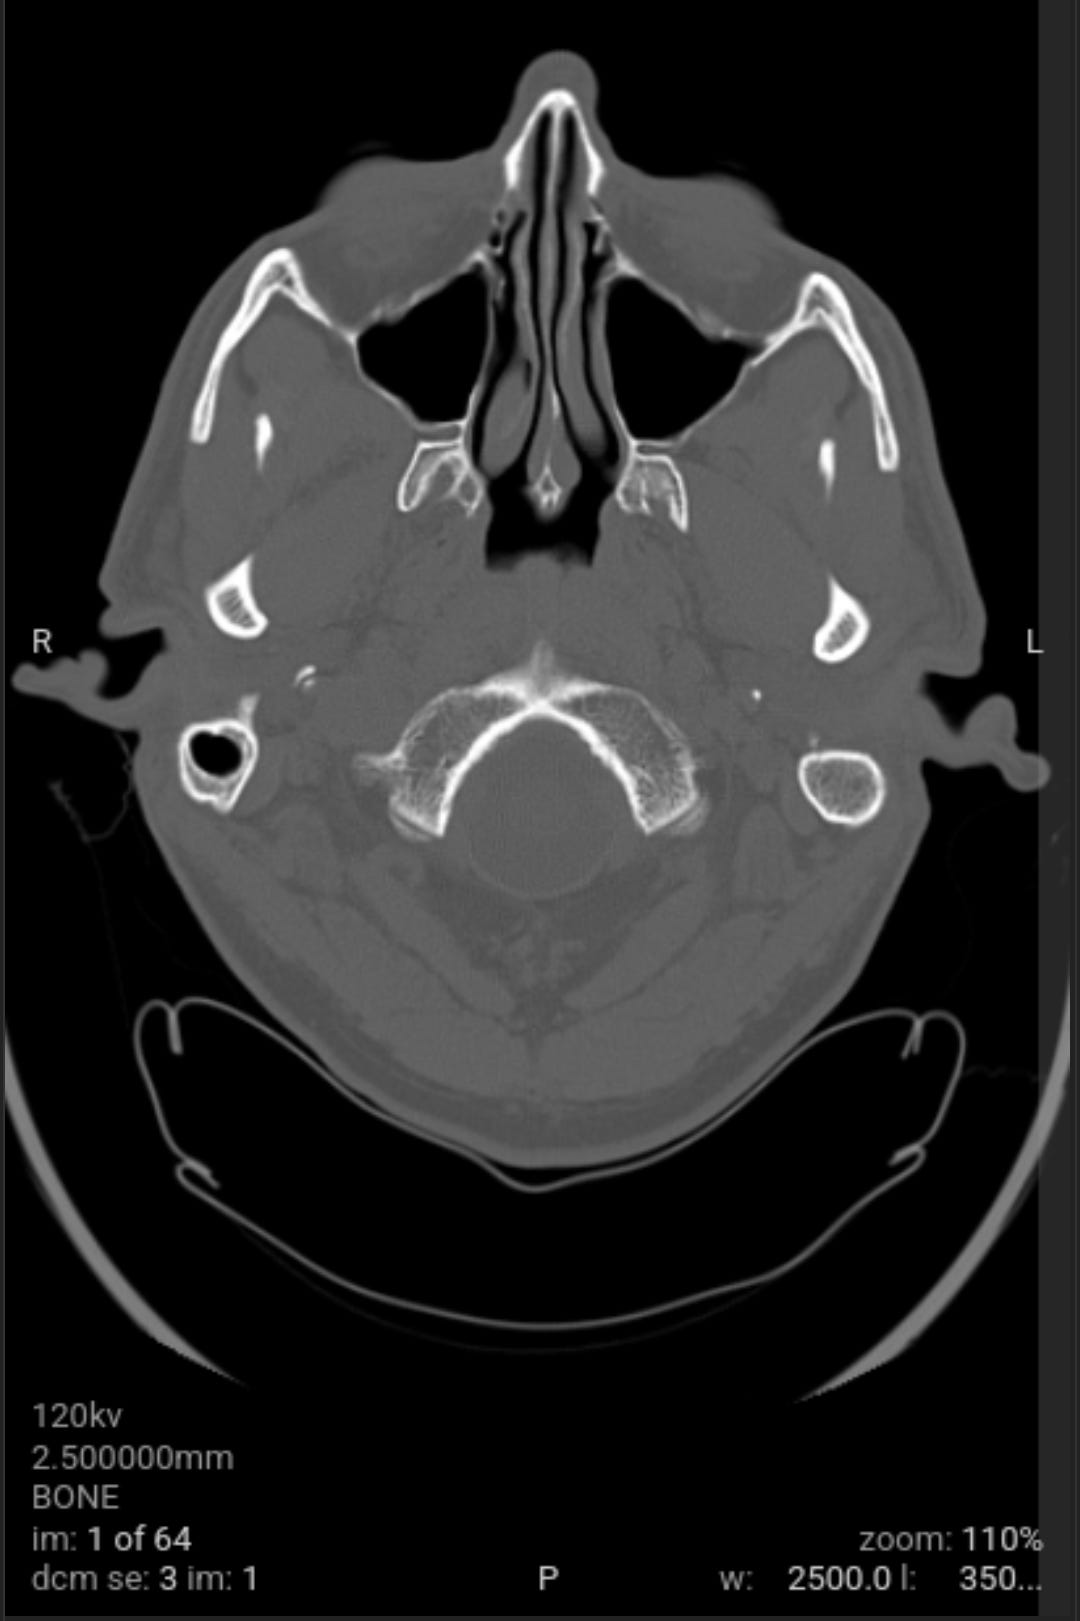

As a followup to eliminate all possible and probably causes of the weaponized audio-video-communications and pathogen nanotechnology. Got blood work and CAT scan done. Results came back good.

As a followup to eliminate all possible and probably causes of the weaponized audio-video-communications CNT and pathogen nanotechnology WPT, I got blood work and CAT scan done yesterday. All came back good with the exception of a low Red Blood Cell RBC count due to my cleansing diet on vegetables and plant based proteins that needs more iron in it with vitamin C, I already dose with vitamin B12 (preference is methylcobalamine). The medical staff could not determine what the unknown material removed from my body was from the salt baths or the material that moved around and itches at times on the left side of my head.

The void spaces on left side are what I suspect to be where the nanotechnology circuitry was removed by magnetic vortex skyrmion unit, chelators, salt water baths, no yeast diet and no added sugar diet. Note the scans do not show any nanotechnology based synthetic biology parasites. This is why the samples pulled from my body were classified as unknown by the western medical staff not trained in the nanotechnology and synthetic biology knowledge domain, a huge gap in Western medicine.